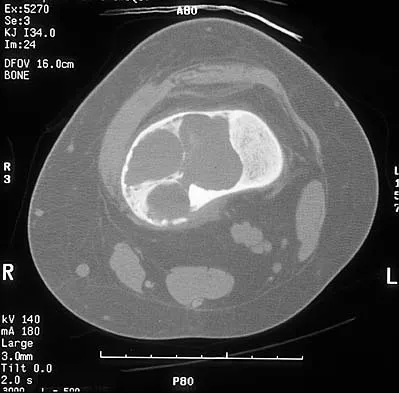

A 14-year-old boy reports pain in the distal thigh. He denies any history of trauma. Examination reveals tenderness and swelling of the distal thigh without effusion. A radiograph and CT scan are shown in Figures 10a and 10b. A biopsy specimen is shown in Figure 10c. Management should consist of

Explanation

Based on these findings, the patient has an aneurysmal bone cyst. Frequently, fluid-fluid levels can be detected on MRI or CT images. The histologic results show a lesion that consists of cavernous spaces filled with blood. The lining of the cavity contains spindle cells, multinucleated giant cells, and reactive bone. Curettage and bone grafting is the preferred treatment method. Without treatment, these lesions can become quite large and destructive. Radiation therapy is not recommended for resectable lesions. Chemotherapy is not required for these benign lesions. Simon MA, Springfield DS, et al: Common Benign Bone Tumors: Surgery for Bone and Soft Tissue Tumors. Philadelphia, PA, Lippincott Raven, 1998, pp 194-200.